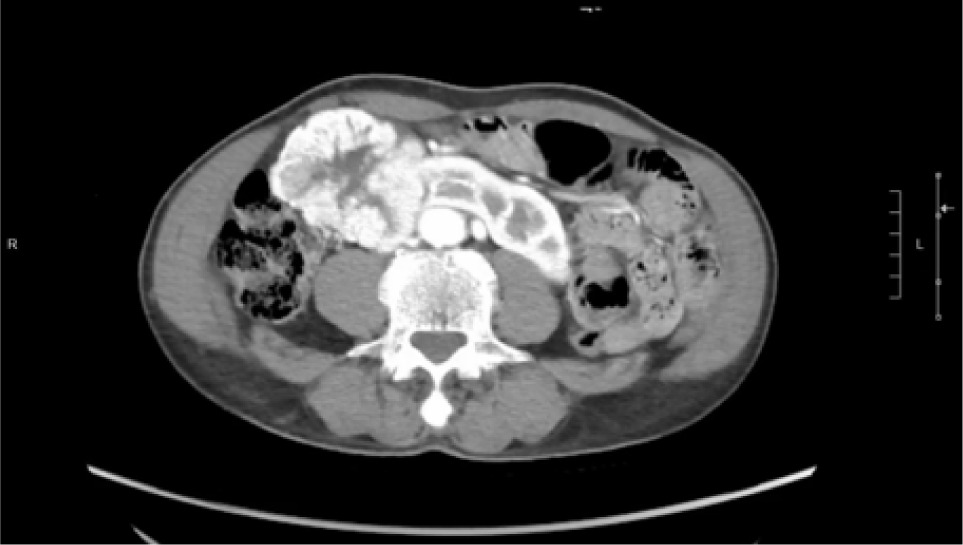

A 74-year-old Chinese male patient, ex-smoker, and social drinker, with a history of carcinoma of prostate in remission with laparoscopic radical prostatectomy done 11 years ago presented with an incidental finding of a right abdominal mass without frank symptoms. Preoperative eGFR ranges from 80 to 90 mL/min/1.73m2. Computed tomography (CT) showed a 7 cm heterogeneous mass on the right side of the HSK with complex hilar anatomy (Figures 1 & 2). Dual tracer (C-11 acetate and F18 FDG) positron emission tomography (PET-CT) showed moderate and mildly avid renal cell carcinoma (RCC) arising from HSK, without nodal or distant metastases. A 3D image reconstruction using FUJIFILM Synapse system was performed, showing complex tumor and vascular anatomy (two renal arteries and an additional artery to isthmus) (Figure 3). An open partial right nephrectomy was planned.

Figure 1: Axial cut of arterial phase-enhanced CT abdomen at the tumor level.